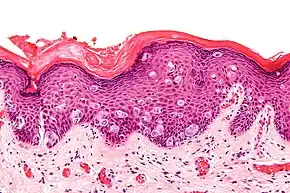

Micrograph of extramammary Paget's disease, H&E stain

Micrograph of extramammary Paget's disease, H&E stain H&E stained micrograph of Extramammary Paget's disease, showing Paget cells infiltrating the epidermis

H&E stained micrograph of Extramammary Paget's disease, showing Paget cells infiltrating the epidermis

EMPD occurs due to an invasion of the epidermis by Paget cells.[2] The cause of the disease is still under debate with recent research indicating that the disease may be associated with Toker cells.[13]

It is important to include that the lesion is associated with another cancer. A biopsy will establish the diagnosis. Punch biopsies are not effective in differentially diagnosing for EMPD and as a result, excisional biopsies of the affected area are taken [XX]. A positive test result for EMPD shows increased numbers of large polygonal cells with a pale bluish cytoplasm, large nucleus and nucleolus, infiltrating the epidermal layer.[7] These neoplastic cells can be found singly scattered or can appear in groups called nests.[7]